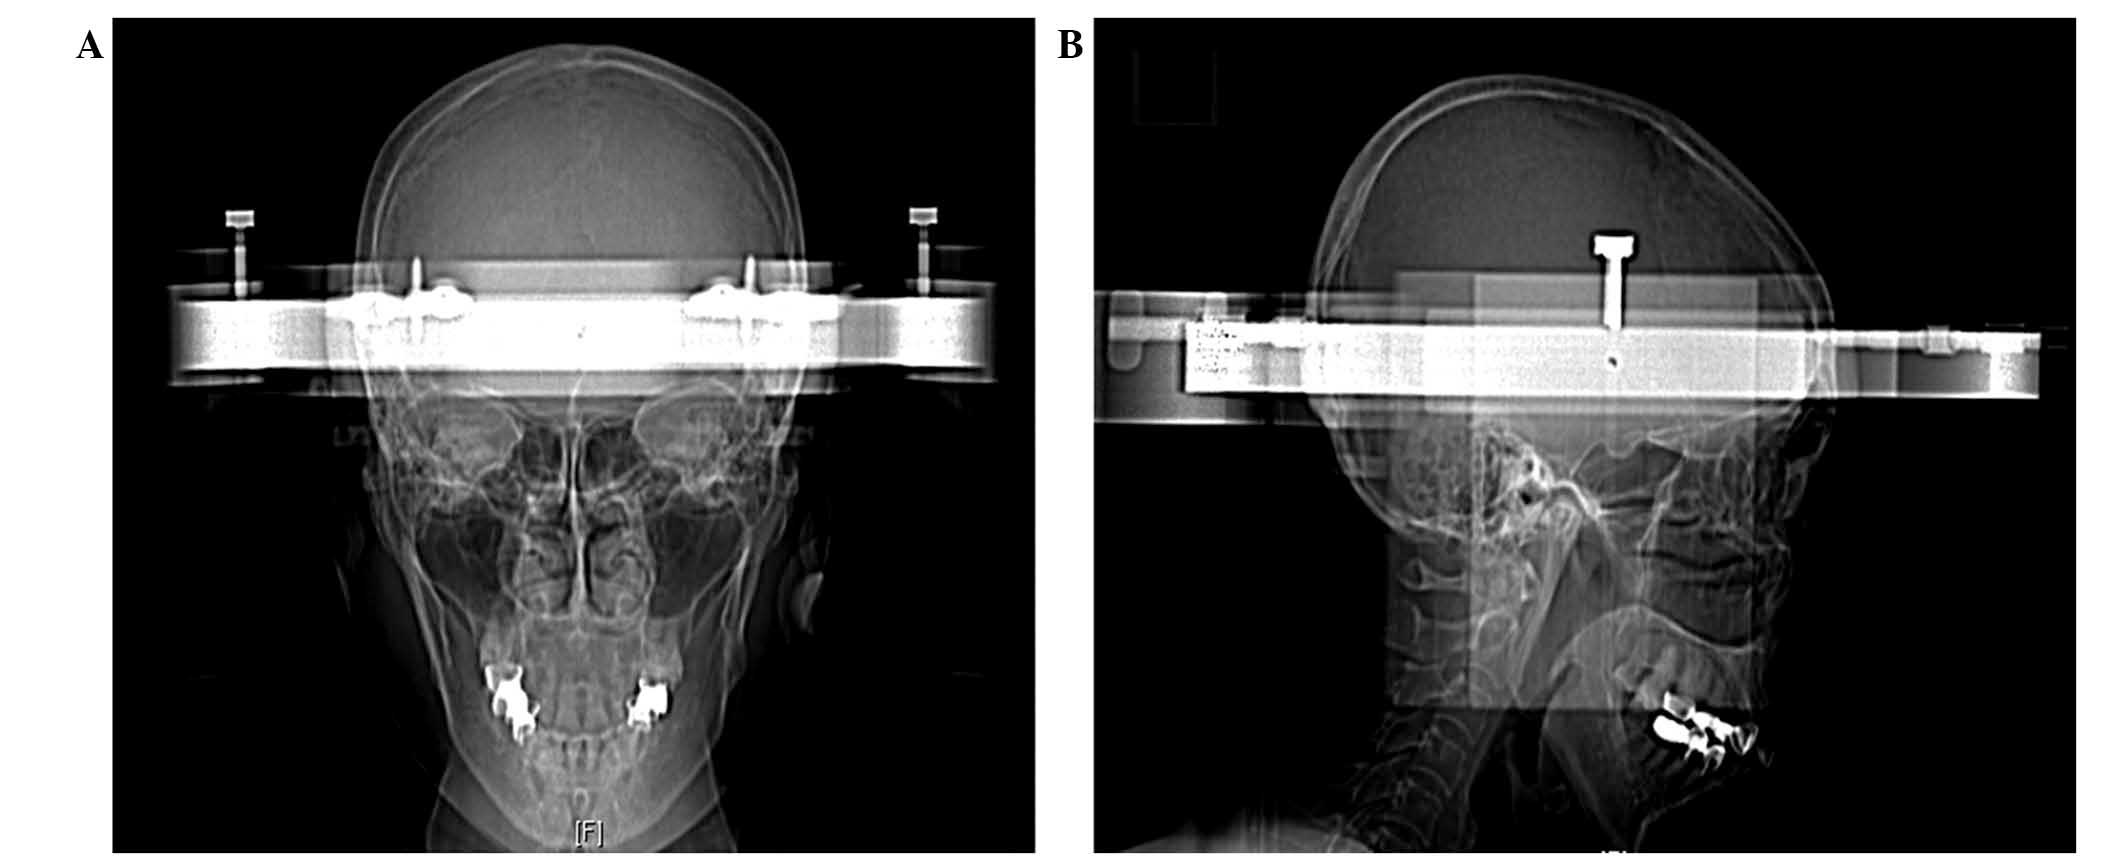

Brainstem metastases have a poor prognosis and are difficult to manage. The present study describes the first case of histopathologically‑confirmed brainstem metastasis originating from lung adenosquamous carcinoma, and discusses the outcomes of treatment by stereotactic aspiration combined with gamma knife radiosurgery (GKRS). A 59‑year‑old female presented with a cystic mass (15x12x13 mm; volume, 1.3 cm3) located in the pons, two years following surgical treatment for adenosquamous carcinoma of the lung. The patient received initial GKRS for the lesion in the pons with a total dose of 54.0 Gy, however, the volume of the mass subsequently increased to 3.9 cm3 over a period of three months. Computed tomography‑guided stereotactic biopsy and aspiration of the intratumoral cyst were performed, yielding 2.0 cm3 of yellow‑white fluid. Histology confirmed the diagnosis of adenosquamous carcinoma. Aspiration provided immediate symptomatic relief, and was followed one week later by repeat GKRS with a dose of 12.0 Gy. The patient survived for 12 months following the repeat GKRS; however, later succumbed to the disease after lapsing into a two‑week coma. The findings of this case suggest that stereotactic aspiration of cysts may improve the effects of GKRS for the treatment of cystic brainstem metastasis; the decrease in tumor volume allowed a higher radiation dose to be administered with a lower risk of radiation‑induced side effects. Therefore, stereotactic aspiration combined with GKRS may be an effective treatment for brainstem metastasis originating from adenosquamous carcinoma.

Figure 3